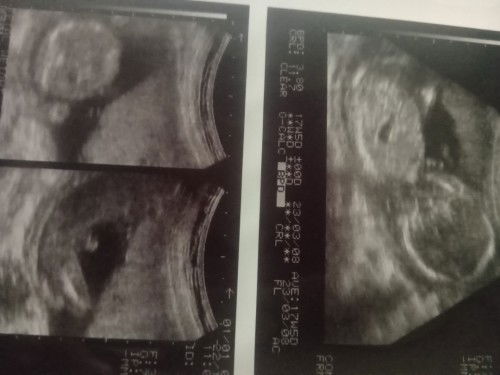

Usg cowo usia 17w

Tadi say usg usia 17w ktnya sih cowo krna kliatan ada yg menonjol , Apa ada yg usg cowo lhir cwe , ap mungkin bisa terjadi yg sprti itu , hehe Brhrapnya sh juga perempuan ,